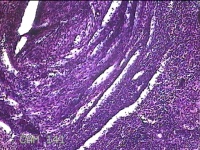

左侧卵巢黄体

性别

女

年龄

34岁

临床诊断

左侧卵巢黄体破裂

一般病史

下腹疼痛11小时。

标本名称

大体所见

灰白暗红色囊壁样组织3x2.3x0.3cm一堆,表面光滑,内壁高低不平,切面灰白暗红色,囊壁厚约0.1cm。